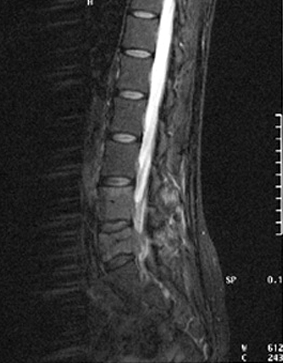

After the treatment, October 11, 2000.

RMN dated October 11, 2000. After the treatment with sodium bicarbonate through lumbar injection we are observing the same section in the fourth image. The noticeable reduction of the local mass can be seen with total elimination of the tumoral mass in the marrow in the inferior sacral area. In the medial area, there is a noticeable reduction with re-canalizing of the medullar channel.

October 11, 2000 – After treatment